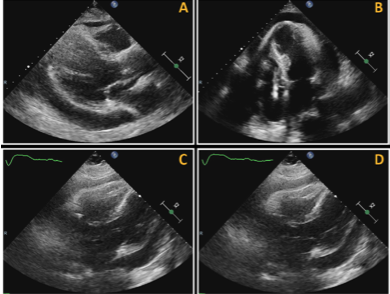

心衰超声心动图,心脏超声心动图

【2019cihfc】周蕾教授:超声心动图在心力衰竭评估中的应用

床旁超声心动图检查发现新发环状心包积液,深度达3cm,伴有轻度的舒张